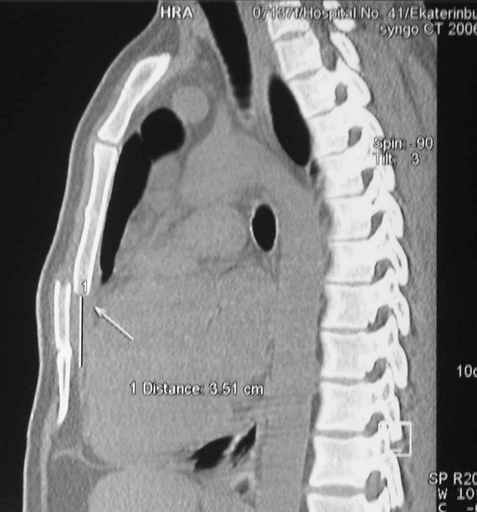

Пару лет назад коллега из грудной хирургии направил больного с хроническими жалобами на боли по поводу ложного сустава грудины.

Оперировали вместе с грудным хирургом и в нашем случае главной причиной была болезненность. Во время операции приняли все меры предосторожности недопущения прокола средостения (см. на 4 снимке близкий контур сердца!!)

Ложный сустав зафиксирован двумя пластинами 2.4 мм (locking plate) позаимствованными из челюстно-лицевой хирургии, с костной пластикой, все остальные пластины мне показались слишком толстыми, грубые для грудины или отсутсвовали возможности создания угловой стабильности.

Рентген снимки во время операции и последние сделаны на днях.